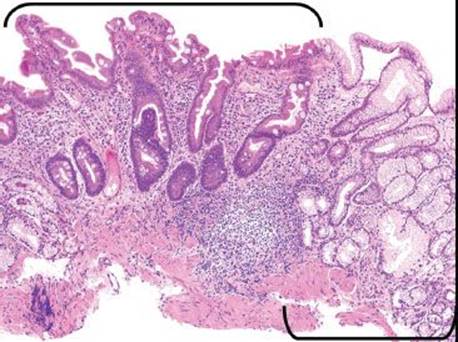

Figure 2.79 Chronic gastritis pattern. Chronic gastritis refers to a heterogeneous group of diseases characterized by chronic inflammation of the gastric mucosa. This is a completely nonspecific injury pattern that relies on clinicopathologic red flags to uncover the underlying etiology.

BASAL LYMPHOCYTIC INFILTRATE SUBPATTERN

This subpattern of chronic gastritis is defined by a low-lying lymphocytic infiltrate that expands the lamina propria between the base of the gastric glands and the muscularis mucosae. The prototypical case shows a “band-like” infiltrate hugging the muscularis mucosae at scanning magnification. High-power examination shows admixed plasma cells and occasional eosinophils, but the dominant cell type is lymphocytes (Figs. 2.79, 2.97 and 2.98).